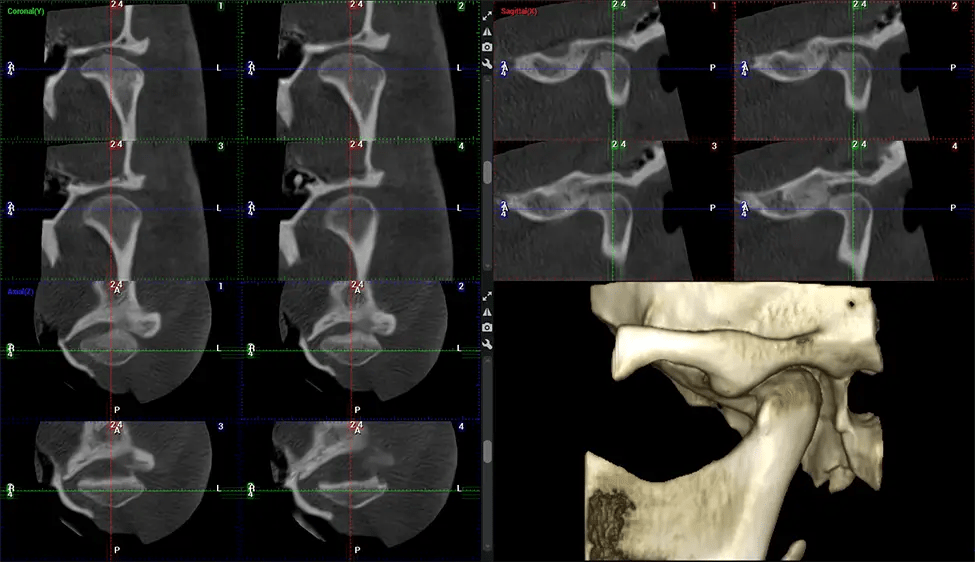

This 3D scan, called cone beam computed tomography, gives your dentist a more complete image of your oral anatomy and disease processes than a traditional X-ray. Unlike conventional X-rays, which capture a 2D image of your mouth from various angles, a 3D scan takes multiple digital X-rays for one image. It provides a complete view of your jaw, teeth, nerves, and soft tissues. This enhanced view allows dentists to detect minor issues not visible in traditional 2D scans, such as impacted wisdom teeth or bone fractures in the sinus cavity.

Another significant benefit is that 3D imaging provides more precise images of your bone structure. These images are more detailed, providing you with a more accurate diagnosis. An accurate diagnosis means better treatment for you.

After the scanning process, the captured X-ray images are processed by the CBCT software, which applies algorithms to reconstruct a detailed 3D image of the scanned area. The software compiles these individual X-ray images and creates a digital 3D representation of the patient’s anatomy. The reconstructed 3D CBCT image can be viewed and analyzed by the dentist or radiologist. This image can be manipulated, rotated, and zoomed in or out to examine specific structures and evaluate the patient’s condition.

Planmeca Viso G7 CBCT ( Cone Beam CT Scan ) is designed to surpass the demands of industry leaders, specialists, and large institutions. It’s has a large ø25×30 cm sensor with four built-in cameras. It can capture unlimited volume sizes from a ø3×3 cm to a ø30x30cm volume capturing the skullcap through C7 on the cervical spine. The Planmeca Viso G7 offers the industry’s largest single volume scan of ø30×19 cm. It’s poised to handle advanced imaging modalities such as Planmeca ProFace® and Planmeca 4D™ Jaw Motion technology. The occipital head support allows an unimpeded view of facial tissue.